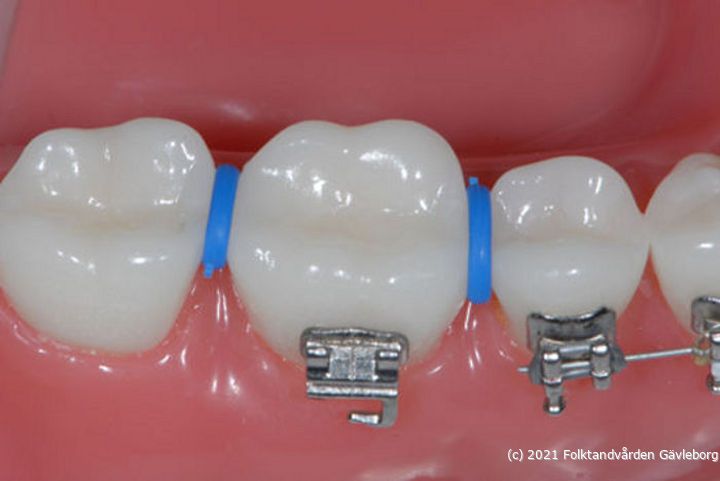

Standardmetoden för att separera tänder är blå separationsringar. De ska placeras i approximalrummet runt kontaktpunkten så att den ena delen ligger under kontaktpunkten och den andra delen ovanför. Separationsringarna trycker isär tänderna något så att vi får plats med band vilket brukar ta 5-7 dagar. Att separera tänder kan ibland krångla vilket t.ex kan bero på att granntänderna inte är fullständigt erupterade. Ibland är det även så trångt att fjädrar i stället måste användas.

• sep02Separationsringar rätt placerade